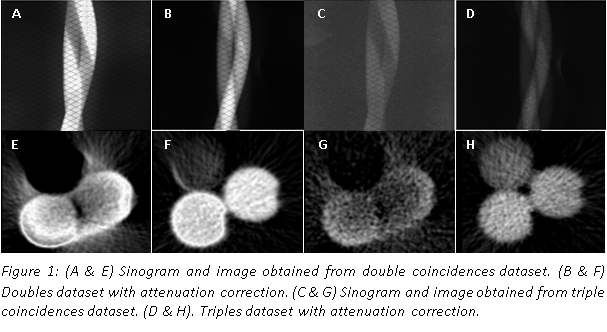

| ABSTRACT | Introduction: Simultaneous in-vivo imaging of several biological processes may improve oncological, neurological and cardiovascular studies by providing complementary information obtained under the same exact conditions and coregistered in space and time. Standard PET imaging does not allow multiplexed acquisitions, as all annihilation photons have the same energy. We developed a technique called multiplexed PET (mPET), which uses a tracer labelled with a pure positron emitter (such as 18 F, 13 N, 11 C), and a tracer labeled with a positrongamma emitter (such as 124 I, 76 Br, 82 Rb, 86 Y). Positrongamma emitters generate a significant number of triplecoincidences , which allows them to be differentiated from the standard PET radionuclides . In this work, we evaluated the performance of mPET using phantom and animal experiments. |

| ABSTRACT | Multiplexed PET (mPET) is a new imaging technique compatible with any existing PET scanner which allows simultaneous imaging of two PET tracers in vivo. In this work we present initial results of a new procedure to measure liquid absorption (LA) in the airways, a promising biomarker for evaluating treatment response in lung diseases. We performed dynamic PET imaging in the lungs of 10 pigs in a clinical PET scanner using inhaled 13N-NH3 and 76Br-Albumin as tracers.

Triple coincidences in PET can be used to enable the simultaneous imaging and separation of radiotracers labeled with standard positron emitters (such as 13N) and positron-gamma emitters (such as 76 Br). We have previously shown that multiplexed PET can be achieved without any kinetic modelling or hardware modification, and therefore it can be used in most current PET scanners. The goal of this study was to demonstrate that this methodology can be applied to solve important clinical needs, such as the quantitative measurement of the liquid absorption in the airways, a new biomarker for the treatment response of Cystic Fibrosis (CF) patients. |